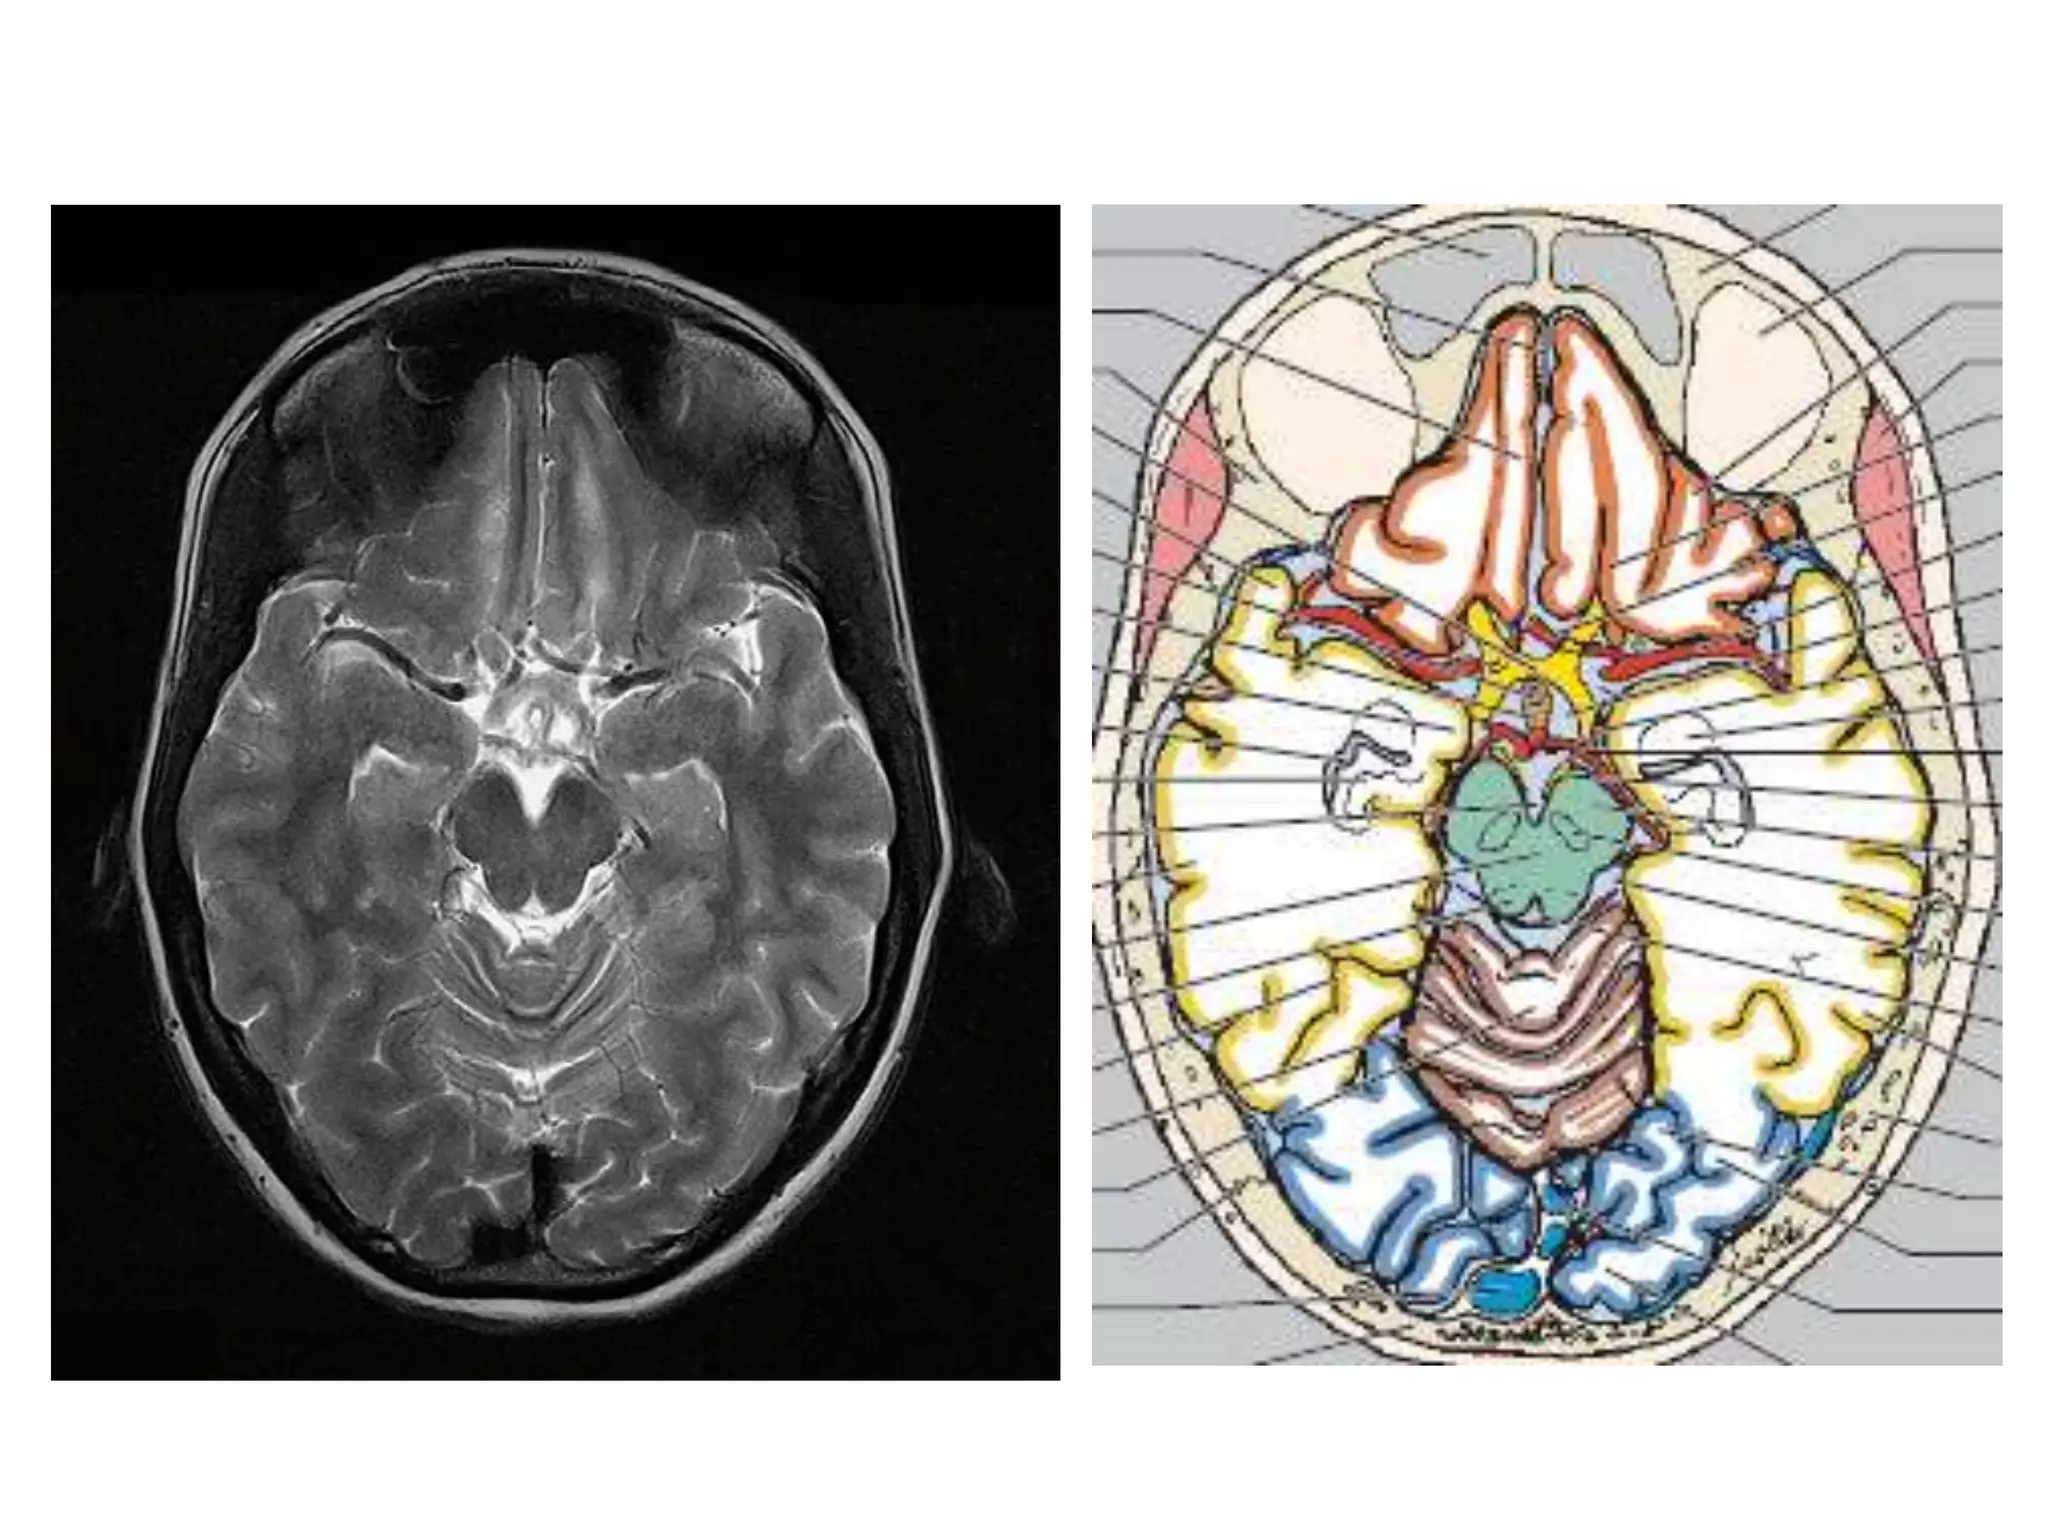

CISTERNS

• Where brain and skull are not closely

apposed, arachnoid and pia separate – and form

cisterns .

• Mainly present at base of brain, around brain stem and

free edge of tentorium.

1.   Posterior fossa cisterns

2.   Basal cisterns

3.   Mesencephalic cisterns

4.   Lateral superior cisterns

SUPRASELLAR / BASAL CISTERNS

1. Interpeduncular cistern : b/w Cerebral peduncles

Basilar A, thalamoperf. A .

2. Chiasmatic / Suprasellar cistern : above sella

ICA, MCA & ACA origin, P comm. A,

antr. Choroidal A; prox. basal V of Rosenthal;

optic chiasma & tract; hypothalamus, infundibulum.

(extends from infundibulum to postr. surface of frontal

lobe and lies b/w uncus on either side.

Contains circle of willis and so SAH seen)

MESENCEPHALIC CISTERNS

1. Ambient cistern : surrounds mid brain. Connects

Suprasellar, pontine & quadrigeminal cisterns.

PCA, BA, SCA, 6th cranial nerve .

2. Quadrigeminal cistern : behind pineal & Q plate

Connects ambient and supr. cerebellar cisterns.

Pineal gland, postr 3rd ventricle, V of Galen, V of Rosenthal.

3. Velum interpositum : above 3rd ventricle; below fornix

& C.callosum (antr. continuation of Quadrigeminal

cistern)

Internal cerebral V, Choroidal arteries .

LATERAL SUPERIOR CISTERNS

1. Sylvian fissure : b/w insula & opercula.

connects medially with suprasellar cistern

MCA, supr. middle cerebral V.

2. Convexity subarachnoid space

contains cortical arteries and veins.